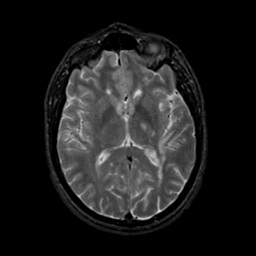

MR Study #21, November 3, 1991 -- Slice #26